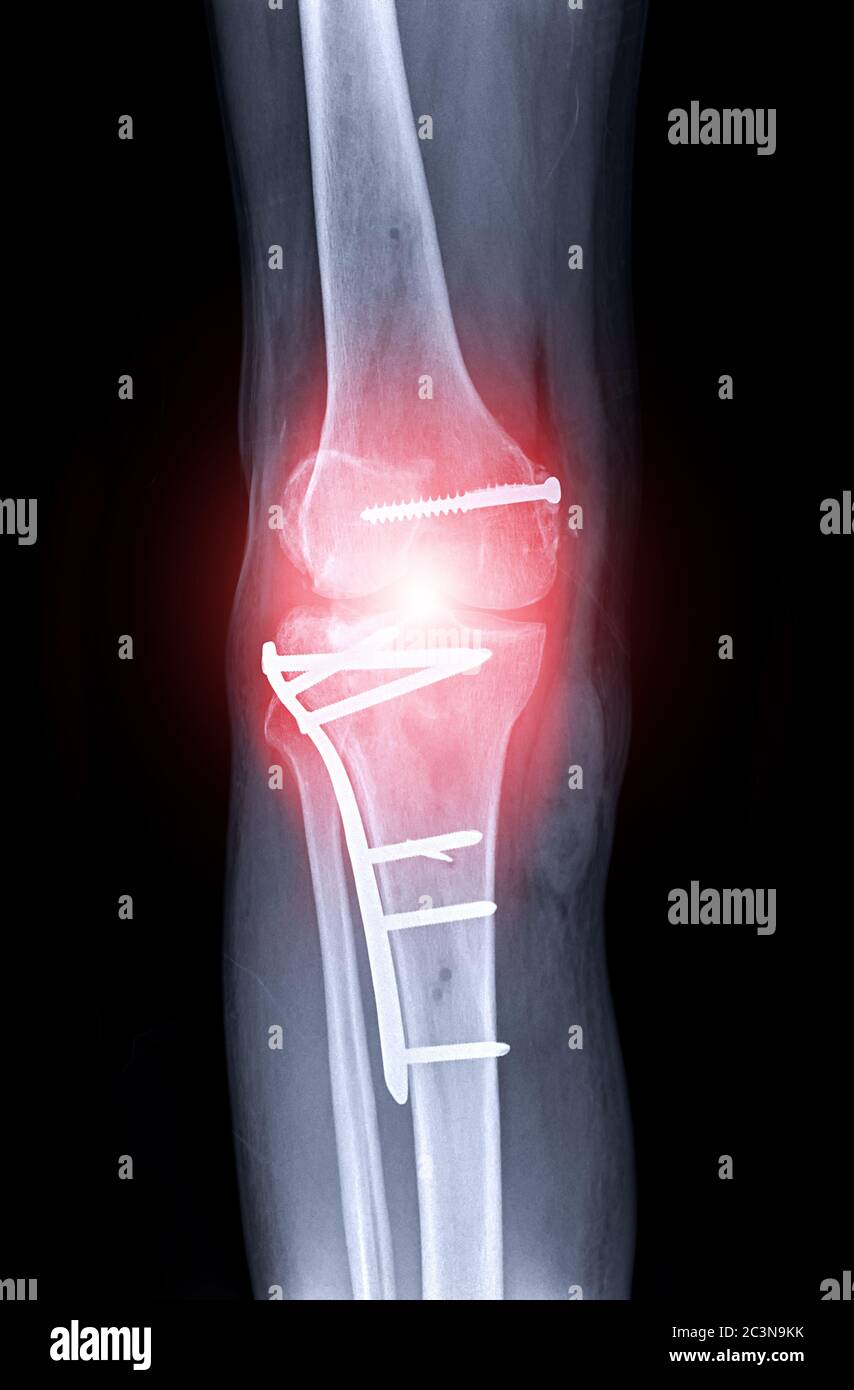

Varón 40 años. Fractura bituberositaria de meseta tibial. Radiografía anteroposterior. Osteosíntesis con placa de soporte, tornillos y cerclaje de alambre en la espina tibial.. que en los últimos años se viene usando con más asiduidad en apoyo de las técnicas de osteosíntesis en las fracturas de meseta tibial es la artroscopia 16-18. Clasificación de Moore. Tipo 1: por separación del platillo tibial medial en el plano coronal. Tipo 2: fractura completa del cóndilo, (el trazo de fractura comienza en el compartimento opuesto que se extiende a través de la eminencia tibial). Tipo 3: fractura marginal por avulsión. Tipo 4: fractura marginal, hundimiento del reborde.